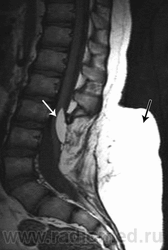

Продолжение.

Приложения:

1.gr_.slayd16.jpg2.pr_.slayd17.jpg3.pr_.slayd18.jpg

Миеломенингоцеле – в грыжевое выпячивание вовлекаются оболочки и спинной мозг. Спинной мозг недоразвит, с участками глиоза, расширенным центральным каналом. Размеры грыжи почти не меняются при пункции.

Характер неврологических симптомов и степень их выраженности определяются уровнем расположения грыжи и степенью вовлечения в процесс спинного мозга. Неврологическая симптоматика чаще всего характеризуется параличами или парезами ног, парезами сфинктеров мочевого пузыря и прямой кишки.

Клиника сопровождается грубыми трофическими расстройствами: отеком стоп, язвами и пролежнями на нижних конечностях и туловище.